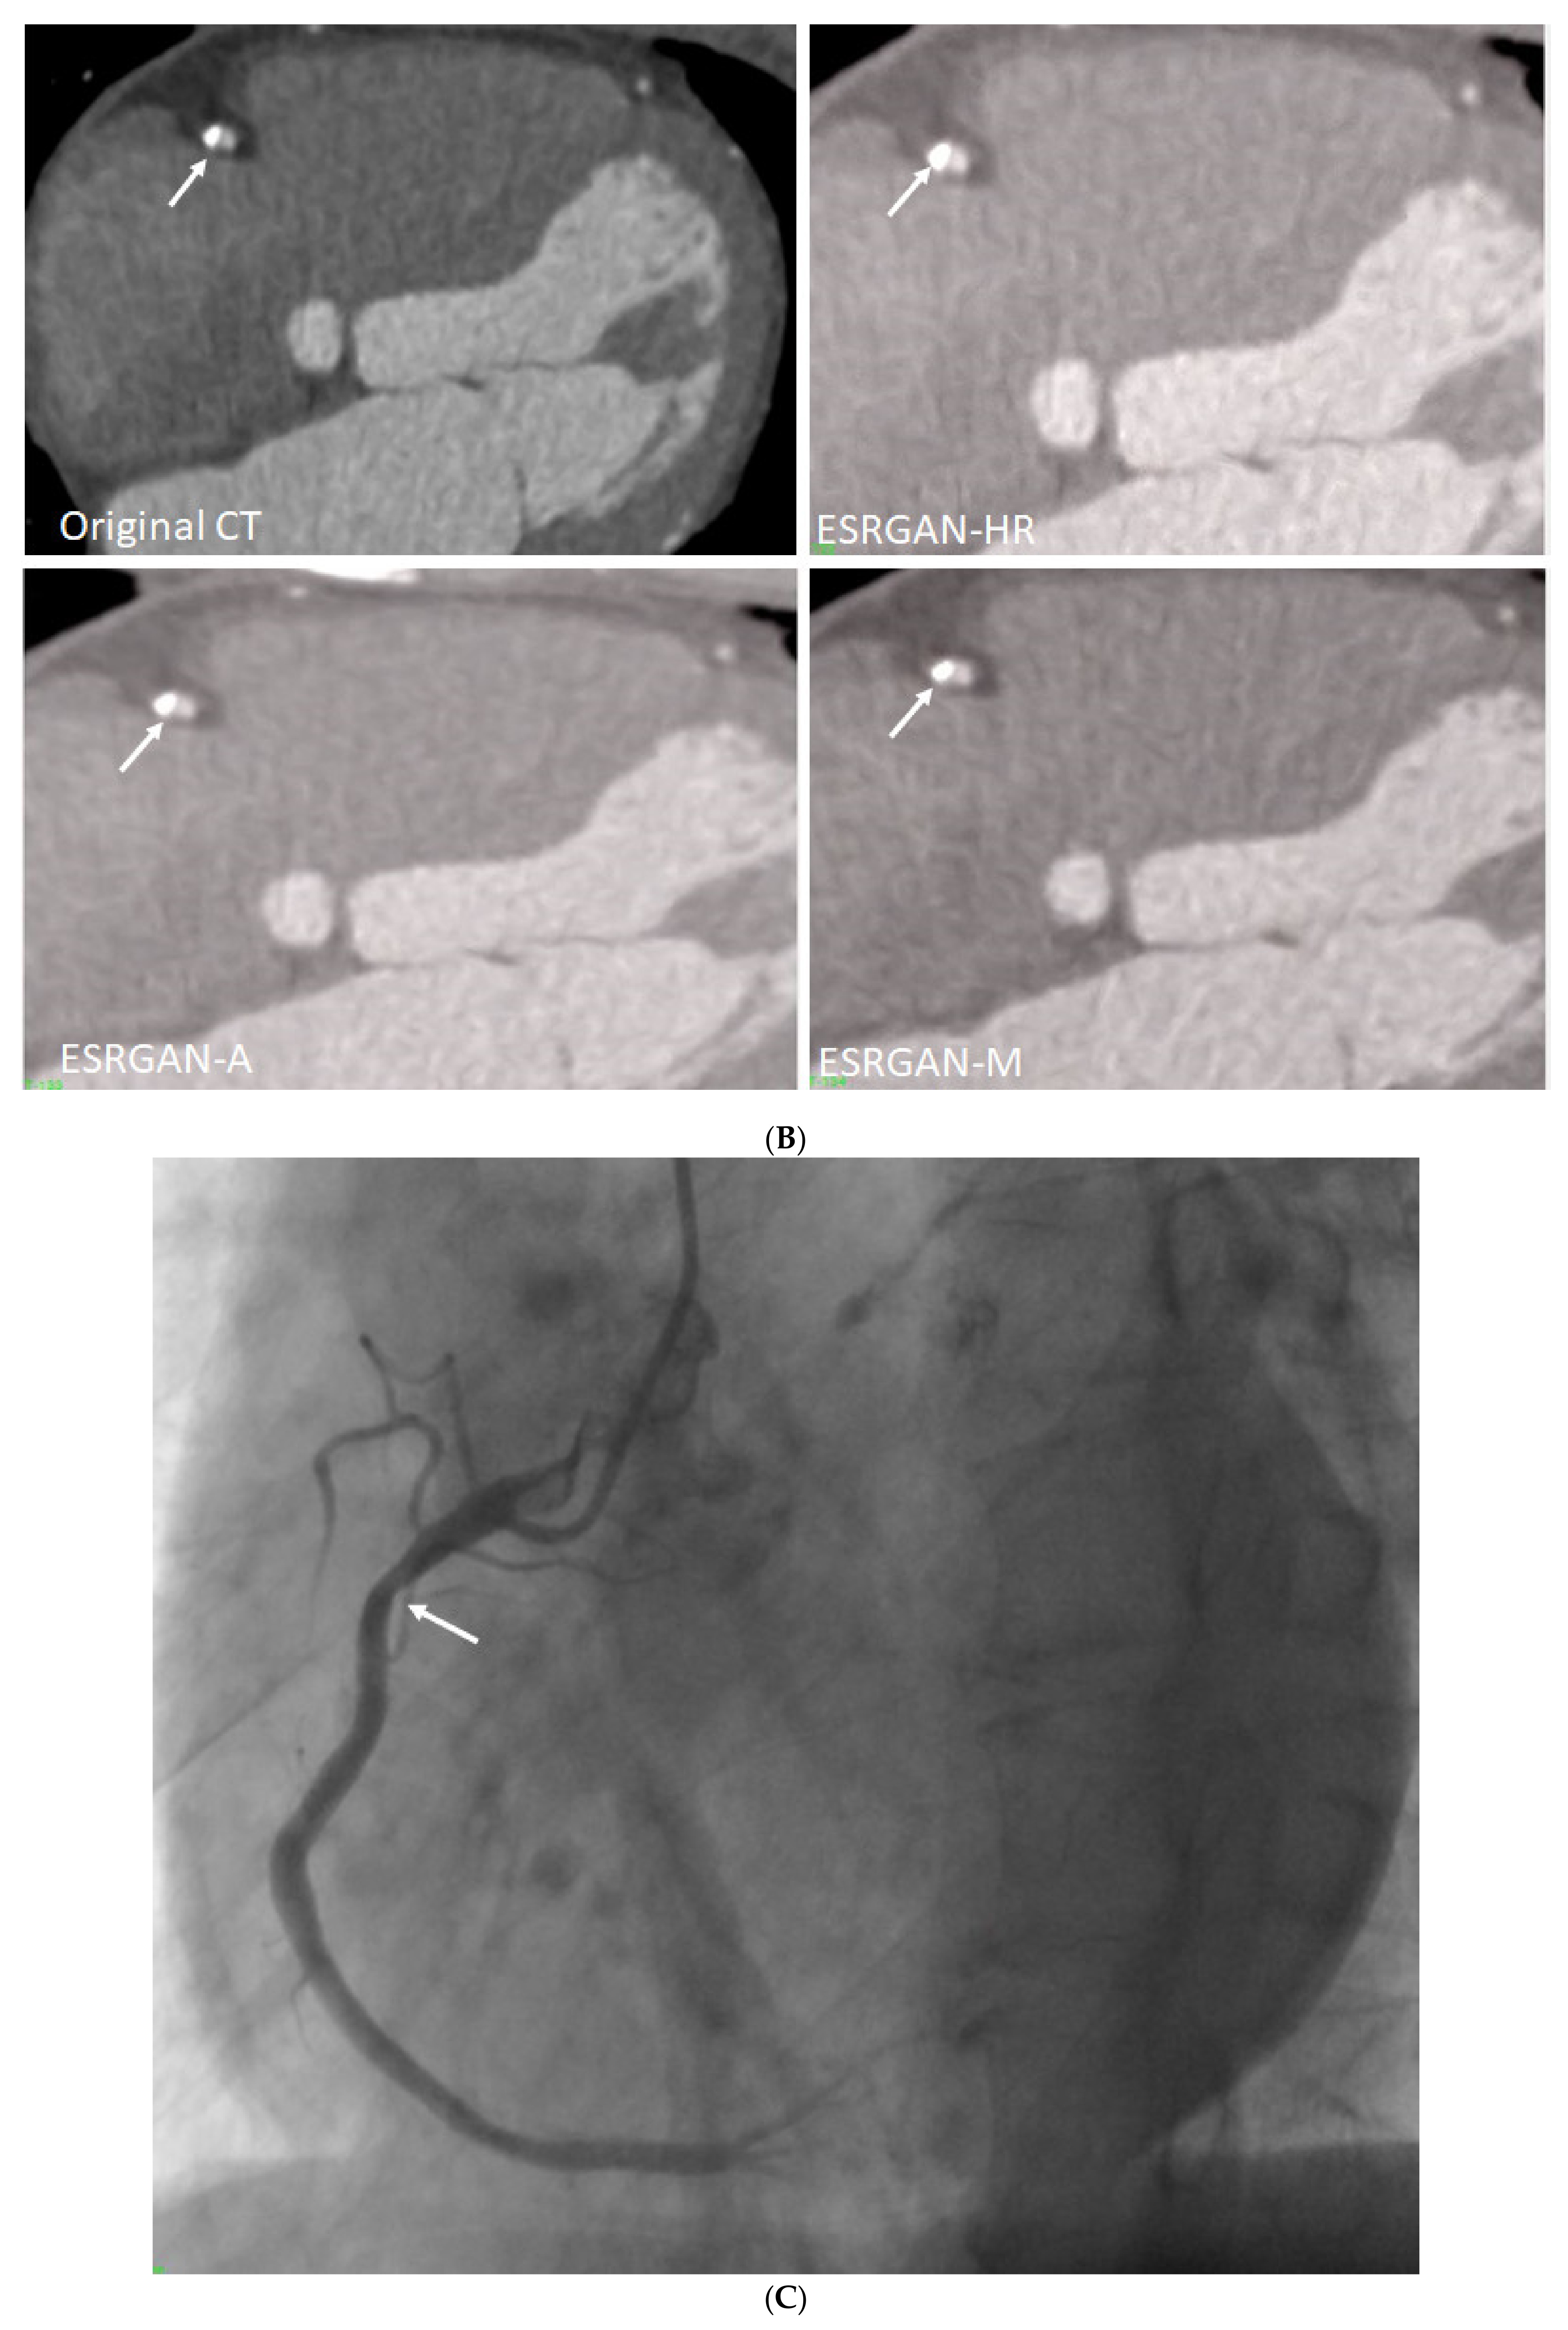

Figure 4 is an example showing multiple calcified plaques at LAD with improvement in the visualisation of coronary lumen observed in ESRGAN-processed images when compared to the original images, while Figure 5 is another example demonstrating multiple calcified plaques at RCA showing improved lumen assessment with ESRGAN-processed images.

Figure 5.

Multiple calcified plaques at the right coronary artery (RCA) in a 64-year-old man with coronary artery disease. (A): Curved planar reformatted image shows multiple calcified plaques at the RCA. Arrow refers to the plaque in the proximal RCA causing >50% stenosis that was selected for comparison of lumen differences. (B): Comparison of the enhanced super-resolution generative adversarial network (ESRGAN)-processed images with original CCTA in the assessment of coronary lumen stenosis caused by the plaque (arrows) as indicated in Figure 4A. The mean lumen stenosis was measured 59%, 52%, 48% and 47% at original CCTA, ESRGAN-High Resolution (ESRGAN-HR), ESRGAN-Average (ESRGAN-A) and ESRGAN-Median (ESRGAN-M) images, respectively. (C): Invasive coronary angiography confirms no significant stenosis with measured diameter of 33% (arrow). ESRGAN-A and M images improved the lumen assessment illustrating no significant stenosis as well.